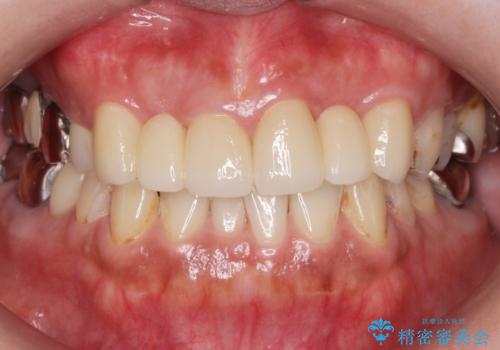

綺麗な被せ物が入りました。

最終的な被せ物は抜歯を行なってから半年経ってから形を整えて型取りを行います。

- ジルコニアクラウンスタンダード・仮歯 13.2万円×6 左上3精密根管治療(リトリートメント)・ファイバーコア 12.1万円費用は治療当時の料金となります